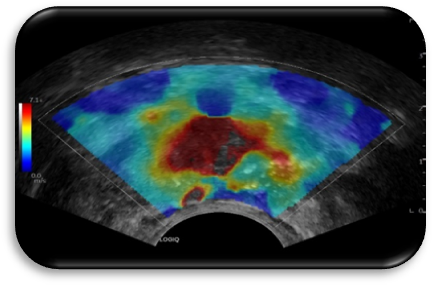

2. 雙模式造影(yǐng)成像技術(shù)

高保真調幅造影(yǐng)、 脈沖反相(xiàng)諧波造影(yǐng)兩種造影(yǐng)模式,在LOGIQ E11全”芯”平台上,幀頻更高,處理速度更快(kuài),可(kě)以捕捉更多病變信息,減少漏診。提高診斷及鑒别診斷準确性。

3. UGAP脂肪肝聲衰減成像。

UGAP通過定量組織的衰減率主要用于肝脂肪變的定量,用于代謝相(xiàng)關性脂肪性肝病的診斷、分(fēn)級、随訪及治療評估等,亦可(kě)爲相(xiàng)關臨床科研提供定量分(fēn)析工(gōng)具。